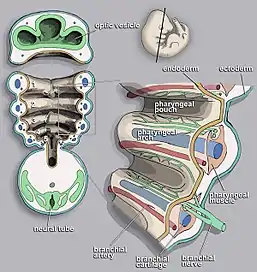

A branchial cleft cyst or simply branchial cyst is a cyst as a swelling in the upper part of neck anterior to sternocleidomastoid. It can, but does not necessarily, have an opening to the skin surface, called a fistula. The cause is usually a developmental abnormality arising in the early prenatal period, typically failure of obliteration of the second, third, and fourth branchial cleft, i.e. failure of fusion of the second branchial arches and epicardial ridge in lower part of the neck. Branchial cleft cysts account for almost 20% of neck masses in children.[1] Less commonly, the cysts can develop from the first, third, or fourth clefts, and their location and the location of associated fistulas differs accordingly.

Branchial cleft cysts are remnants of embryonic development and result from a failure of obliteration of one of the branchial clefts, which are homologous to the structures in fish that develop into gills.[3][4]

Four branchial clefts (also called "grooves") form during the development of a human embryo. The first cleft normally develops into the external auditory canal,[8] but the remaining three arches are obliterated and have no persistent structures in normal development. Persistence or abnormal formation of these four clefts can all result in branchial cleft cysts which may or may not drain via sinus tracts.